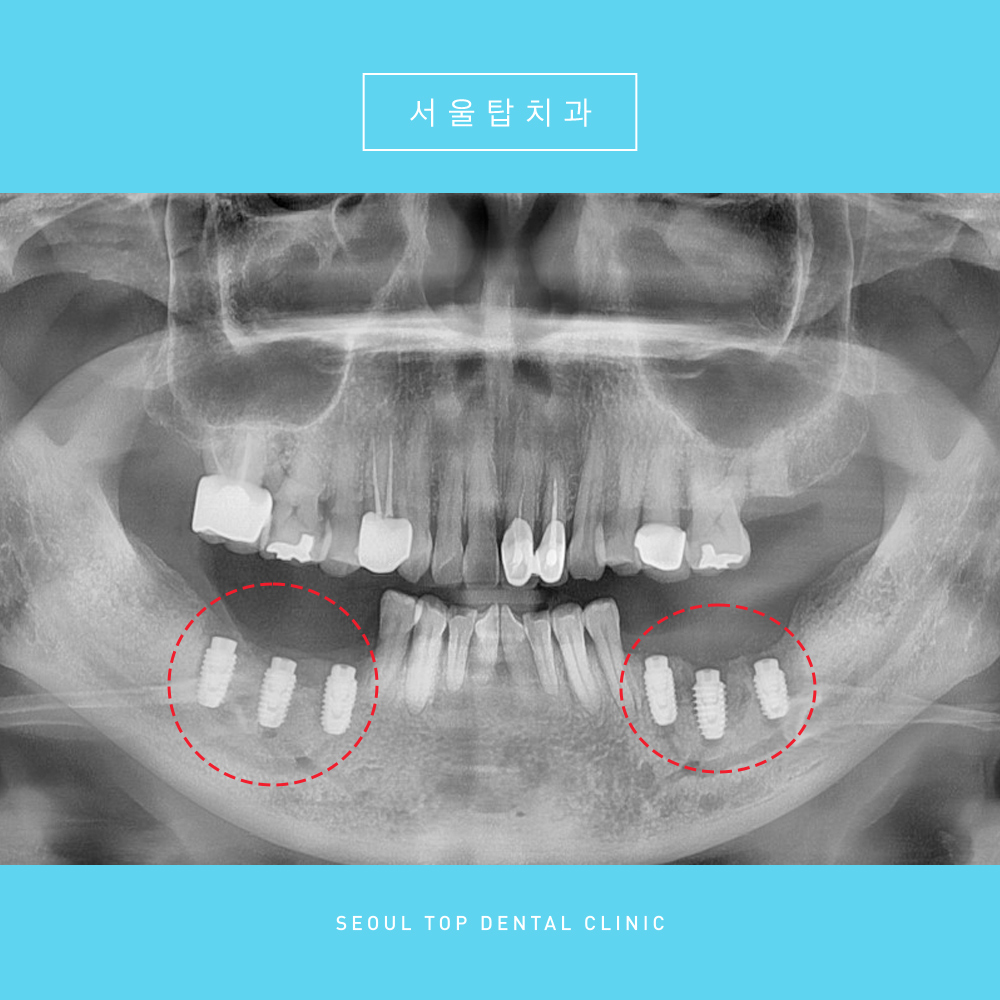

파노라마 사진을 촬영해 체크해보니

구강 내 상태가 매우 심각하였습니다.

양측 아래 과거 타원에서 임플란트 치료를

받으셨다고 하셨는데요.

임플란트 주변으로 염증이 심하였고,

특히 주황색 표시의

오른쪽 가장 후방의 임플란트는

염증으로 인해 잇몸뼈가 다 녹아

임플란트 머리 부분과 뿌리 부분이

분리가 된 상태였습니다.

파노라마상 건강한 잇몸뼈는

하얗게 비춰보여야 하는데,

빨간색 표시의 임플란트 주변을 보시면

까맣게 비춰보이는 염증을 확인할 수 있답니다.

더불어 파란색 표시의 과거 크라운 치료를 받은

왼쪽 작은 어금니에도

염증 소견이 관찰되었습니다.

임플란트 주위염과, 작은어금니의 치주염으로

해당 치아들은 잇몸뼈가 너무 많이 녹아있어

발치가 불가피하였답니다. 😭

해당 파노라마는

뼈이식까지 마무리 한 파노라마 사진인데요.

충분한 기반이 갖춰진 상태가 되면

임플란트 식립을 도와드리기로 했습니다.